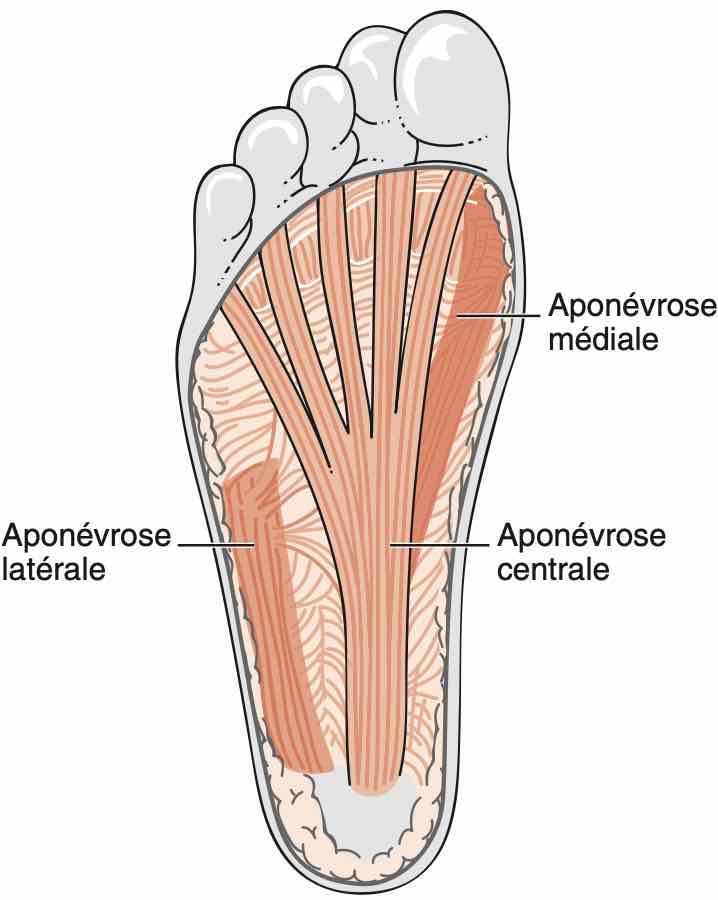

Talalgies

Respect de l'échostructure des aponévroses plantaires, sans épaississement.